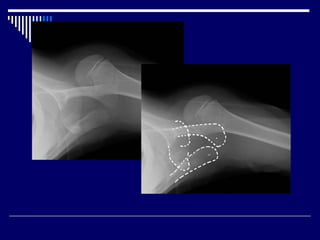

Hill-Sachs lesions

Bankart lesion

• #15 Hill-Sachs lesions are a posterolateral humeral head compression fracture secondary to recurrent anterior shoulder dislocations, as the humeral head comes to rest against the anteroinferior part of the glenoid. It is often associated with a Bankart lesion of the glenoid. Bankart lesions are up to 11 times more common in patients with a Hill-Sachs lesion, with increasing incidence with increasing size A Bankart lesion results from detachment of the anterior inferior labrum from the underlying glenoid, and is usually as a result of previous anterior shoulder dislocation

• #16 A large bony defect is noted in frontal view; involving posterior aspect of humeral head. No dislocation is noted. No lytic bony lesion is noted. previous history of anterior dislocation demonstrates a contour abnormality suggestive of a Hill-Sachs lesion.  X-ray Normal shoulder AP

• #17 A small bone fragment is displaced from the inferior aspect of the glenoid consistent with a bony Bankart lesion. There is also subtle compression deformity of the superolateral humeral head consistent with a Hill-Sachs lesion. Both these lesions are the result of previous anterior shoulder dislocation. This patient had a history of recurrent dislocations.  A Bankart lesion results from detachment of the anterior inferior labrum from the underlying glenoid, and is usually as a result of previous anterior shoulder dislocation, and are associated with matching humeral lesion: the Hill-Sachs defect.

• #62 Bankart fracture This is a post-reduction view. Notice the very large fracture of the glenoid rim with displacement. Hill-Sachs is a posterolateral depression of the humeral head.